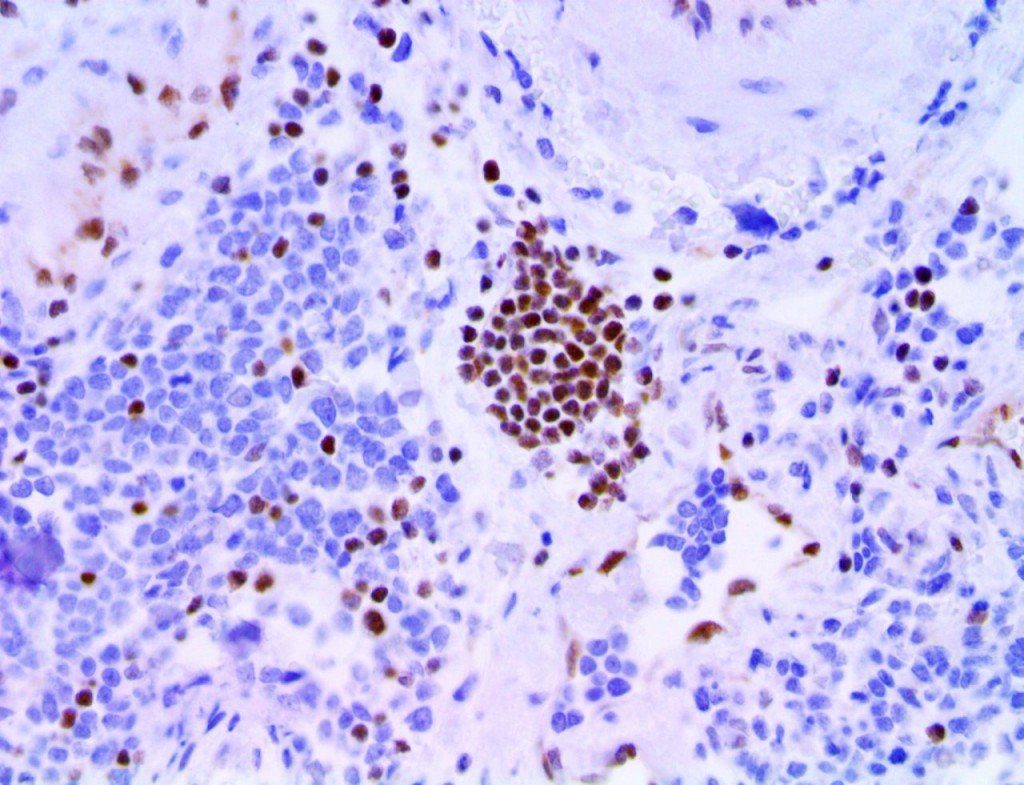

It is the ICU physician who is most likely to witness one of the deadliest manifestations of the abnormal immunological response, the cytokine storm syndrome (CSS). This response is also referred to by some as the cytokine release syndrome (CRS). CSS is characterized by continuous activation and expansion of macrophage and lymphocyte populations, which secrete large amounts of cytokines, causing the cytokine storm. This massive cytokine release is akin to hemophagocytic lymphohistiocytosis (HLH) disease, a syndrome characterized by initial unchecked and persistent activation of cytotoxic T lymphocytes and NK cells.

Clinical and laboratory manifestations of HLH include fever, enlarged liver and/or spleen, neurologic dysfunction, coagulopathy, liver dysfunction, cytopenias (i.e., low levels of erythrocytes, leukocytes, and/or platelets), hypertriglyceridemia, hyperferritinemia, hemophagocytosis, and eventually diminished NK cell activity as the immune system becomes progressively paralyzed. HLH can be familial (primary HLH) or secondary to another disease process (sHLH), such as rheumatic disease, in which it is referred to as macrophage activation syndrome (MAS, characterized by elevated ferritin).